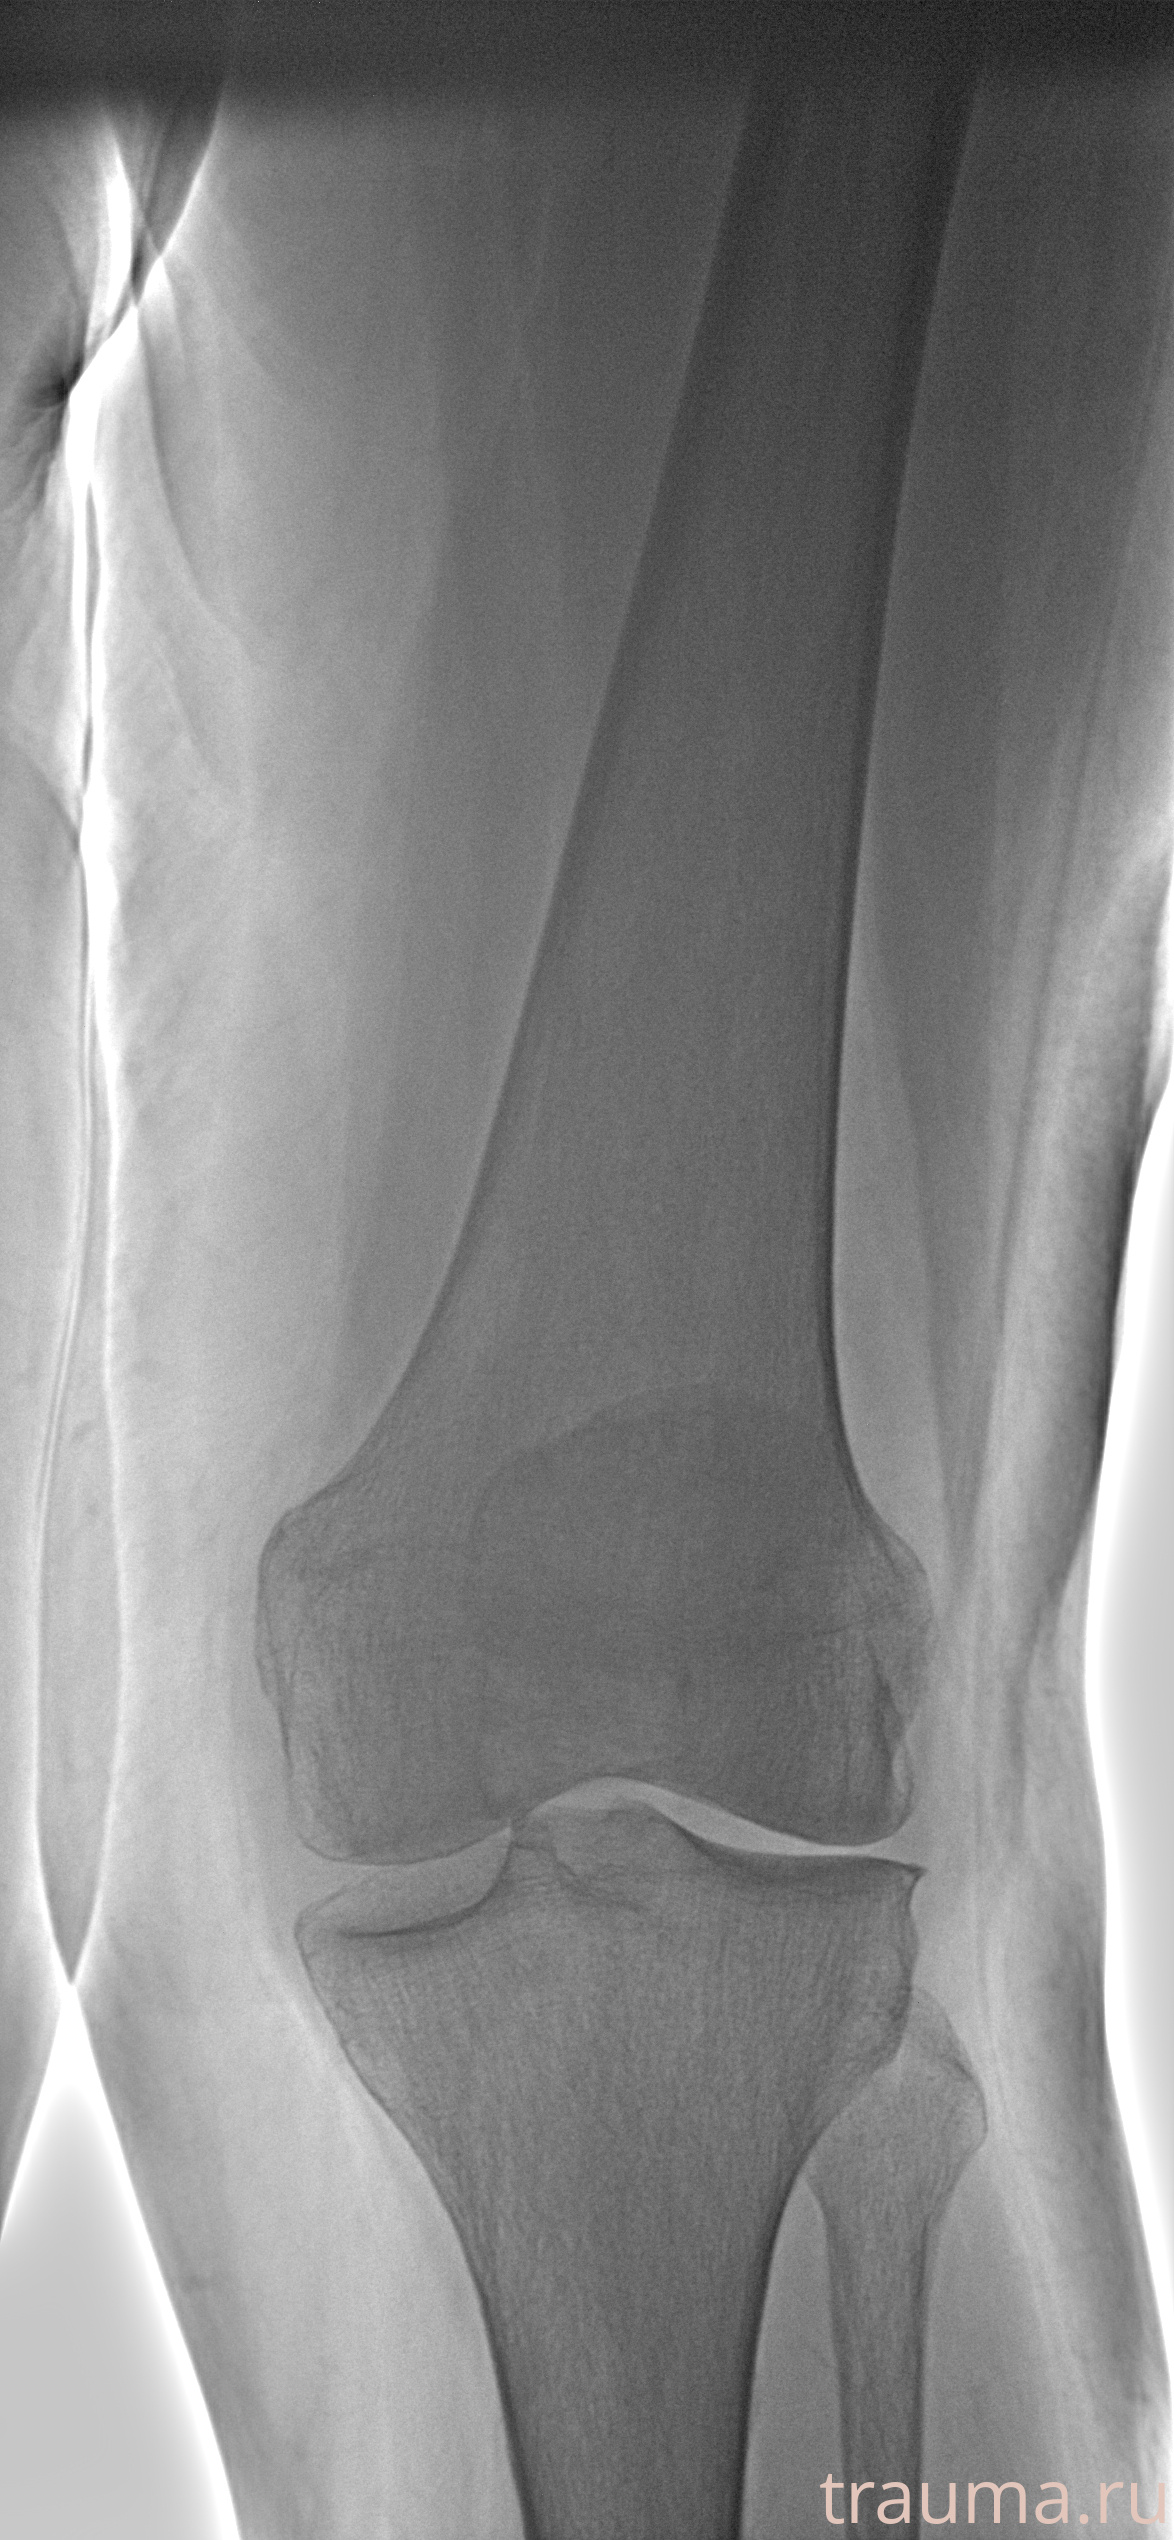

Левая

Рентгенограммы

Рентген на дому: по вашему адресу приезжает врач-рентгенолог, травматолог-ортопед с мобильным рентгеновским аппаратом, проводит диагностику травмы или заболевания, делает необходимые рентгенограммы, дает рекомендации по дальнейшему лечению. Получить качественные снимки в домашних условиях возможно благодаря уникальной методике, разработанной МосРентген Центром для института  Склифосовского